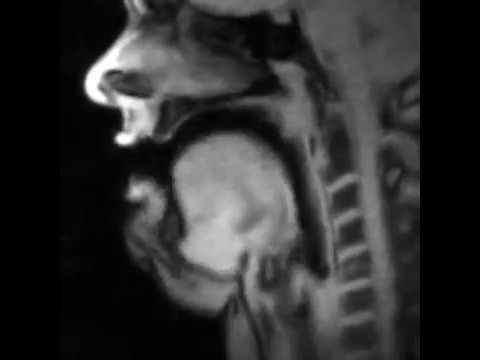

Για να γιορτάσει την αναγνώρισή του, το ινστιτούτο κυκλοφόρησε κάποια βίντεο από μαγνητικό τομογράφο, σε πραγματικό χρόνο, ανθρώπων που μιλούσαν και τραγουδούσαν. Μπορείτε να δείτε τα χείλη, τη γλώσσα, τη μαλακή υπερώα και τον λάρυγγα να κινούνται μαζί, για να σχηματίσουν λέξεις – όλα στα γερμανικά. Είναι πολύ περίεργο.

Ανάρτησαν, επίσης, το βίντεο ενός θώρακα, το οποίο είναι κατά κάποιον τρόπο λιγότερο δυσάρεστο από εκείνο που απεικονίζει το εσωτερικό του κεφαλιού ενός ανθρώπου. Όπως και ο προσομοιωτής στόματος «Ροζ Τρομπόνι», τα βίντεο από το εσωτερικό του στόματος είναι αρκετά τρομακτικά. Το να παρακολουθείς τις εσωτερικές λειτουργίες ενός πράγματος που οι περισσότεροι άνθρωποι κάνουν φυσικά κάθε μέρα, είναι κάτι που σε κάνει να νιώθεις άβολα. Εάν ξεκινήσω να σκέφτομαι συνεχώς την αίσθηση που έχει η γλώσσα μου την ώρα που μιλάω, πιθανότατα θα αναπτύξω κάποια σοβαρή αγχώδη διαταραχή γύρω από την ομιλία.

Παρόλο που είναι σιχαμερά, αυτά τα βίντεο εξυπηρετούν έναν ανώτερο σκοπό στον τομέα της ιατρικής, πέρα από το να μας κάνουν να αηδιάζουμε στο YouTube. Η τεχνολογία μαγνητικής τομογραφίας σε πραγματικό χρόνο καθιστά δυνατή την άμεση παρακολούθηση πραγμάτων, όπως οι αρθρώσεις, ο λόγος, η κατάποση και οι καρδιακοί παλμοί. Η εξωτερική παρακολούθηση βοηθά τους γιατρούς να κάνουν διάγνωση και να αντιμετωπίζουν παθήσεις, όπως τις καούρες ή τον θωρακικό πόνο, χωρίς περαιτέρω επεμβατικές τεχνικές.